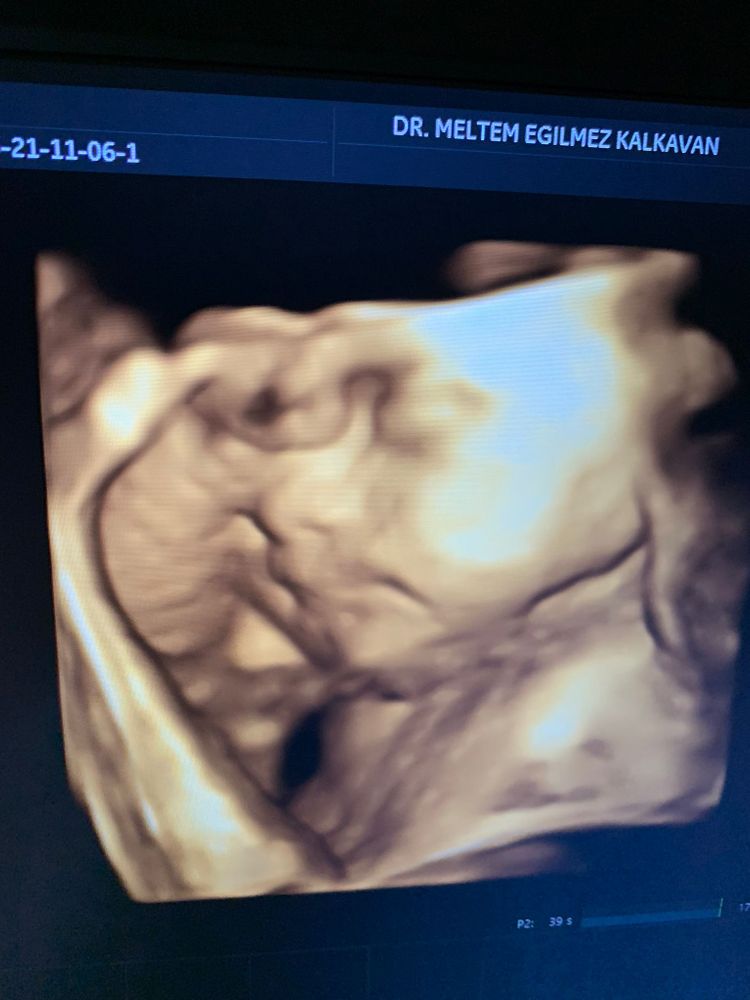

Вот наш младшенький)

Вес 1690.лежит, ручки ножки все возле лица) губки поджал или будут как у меня маленькие, а не как у папы со старшим большие и красивые 🤭